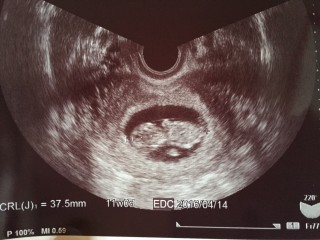

どんどん大きくなる姿にいつもびっくりします。大きさは37.5mmで少し大きめかな。笑

赤ちゃん寝ちゃってるねー!って、言われました♪ 私に似てのんびり屋さんかも。 次は2週間後です。